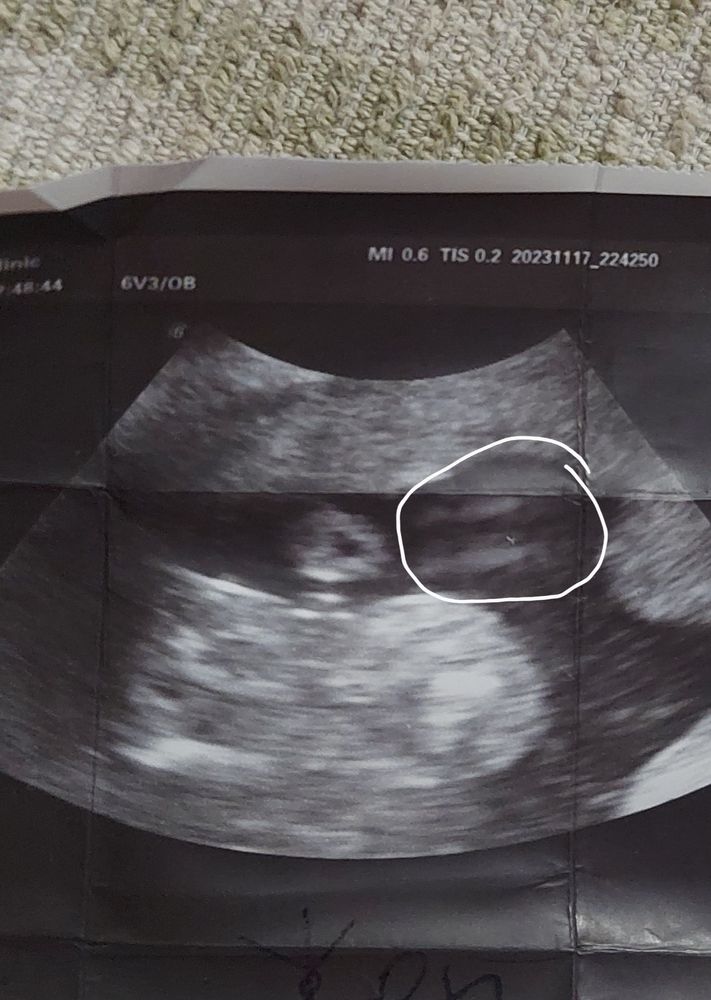

А это мое фото с УЗИ и я "орешек " девчачий якобы обвела что б вам было понятнее. И вот тоже это белое пятно... Может все-таки мальчик? Это похоже и на яички 🤔